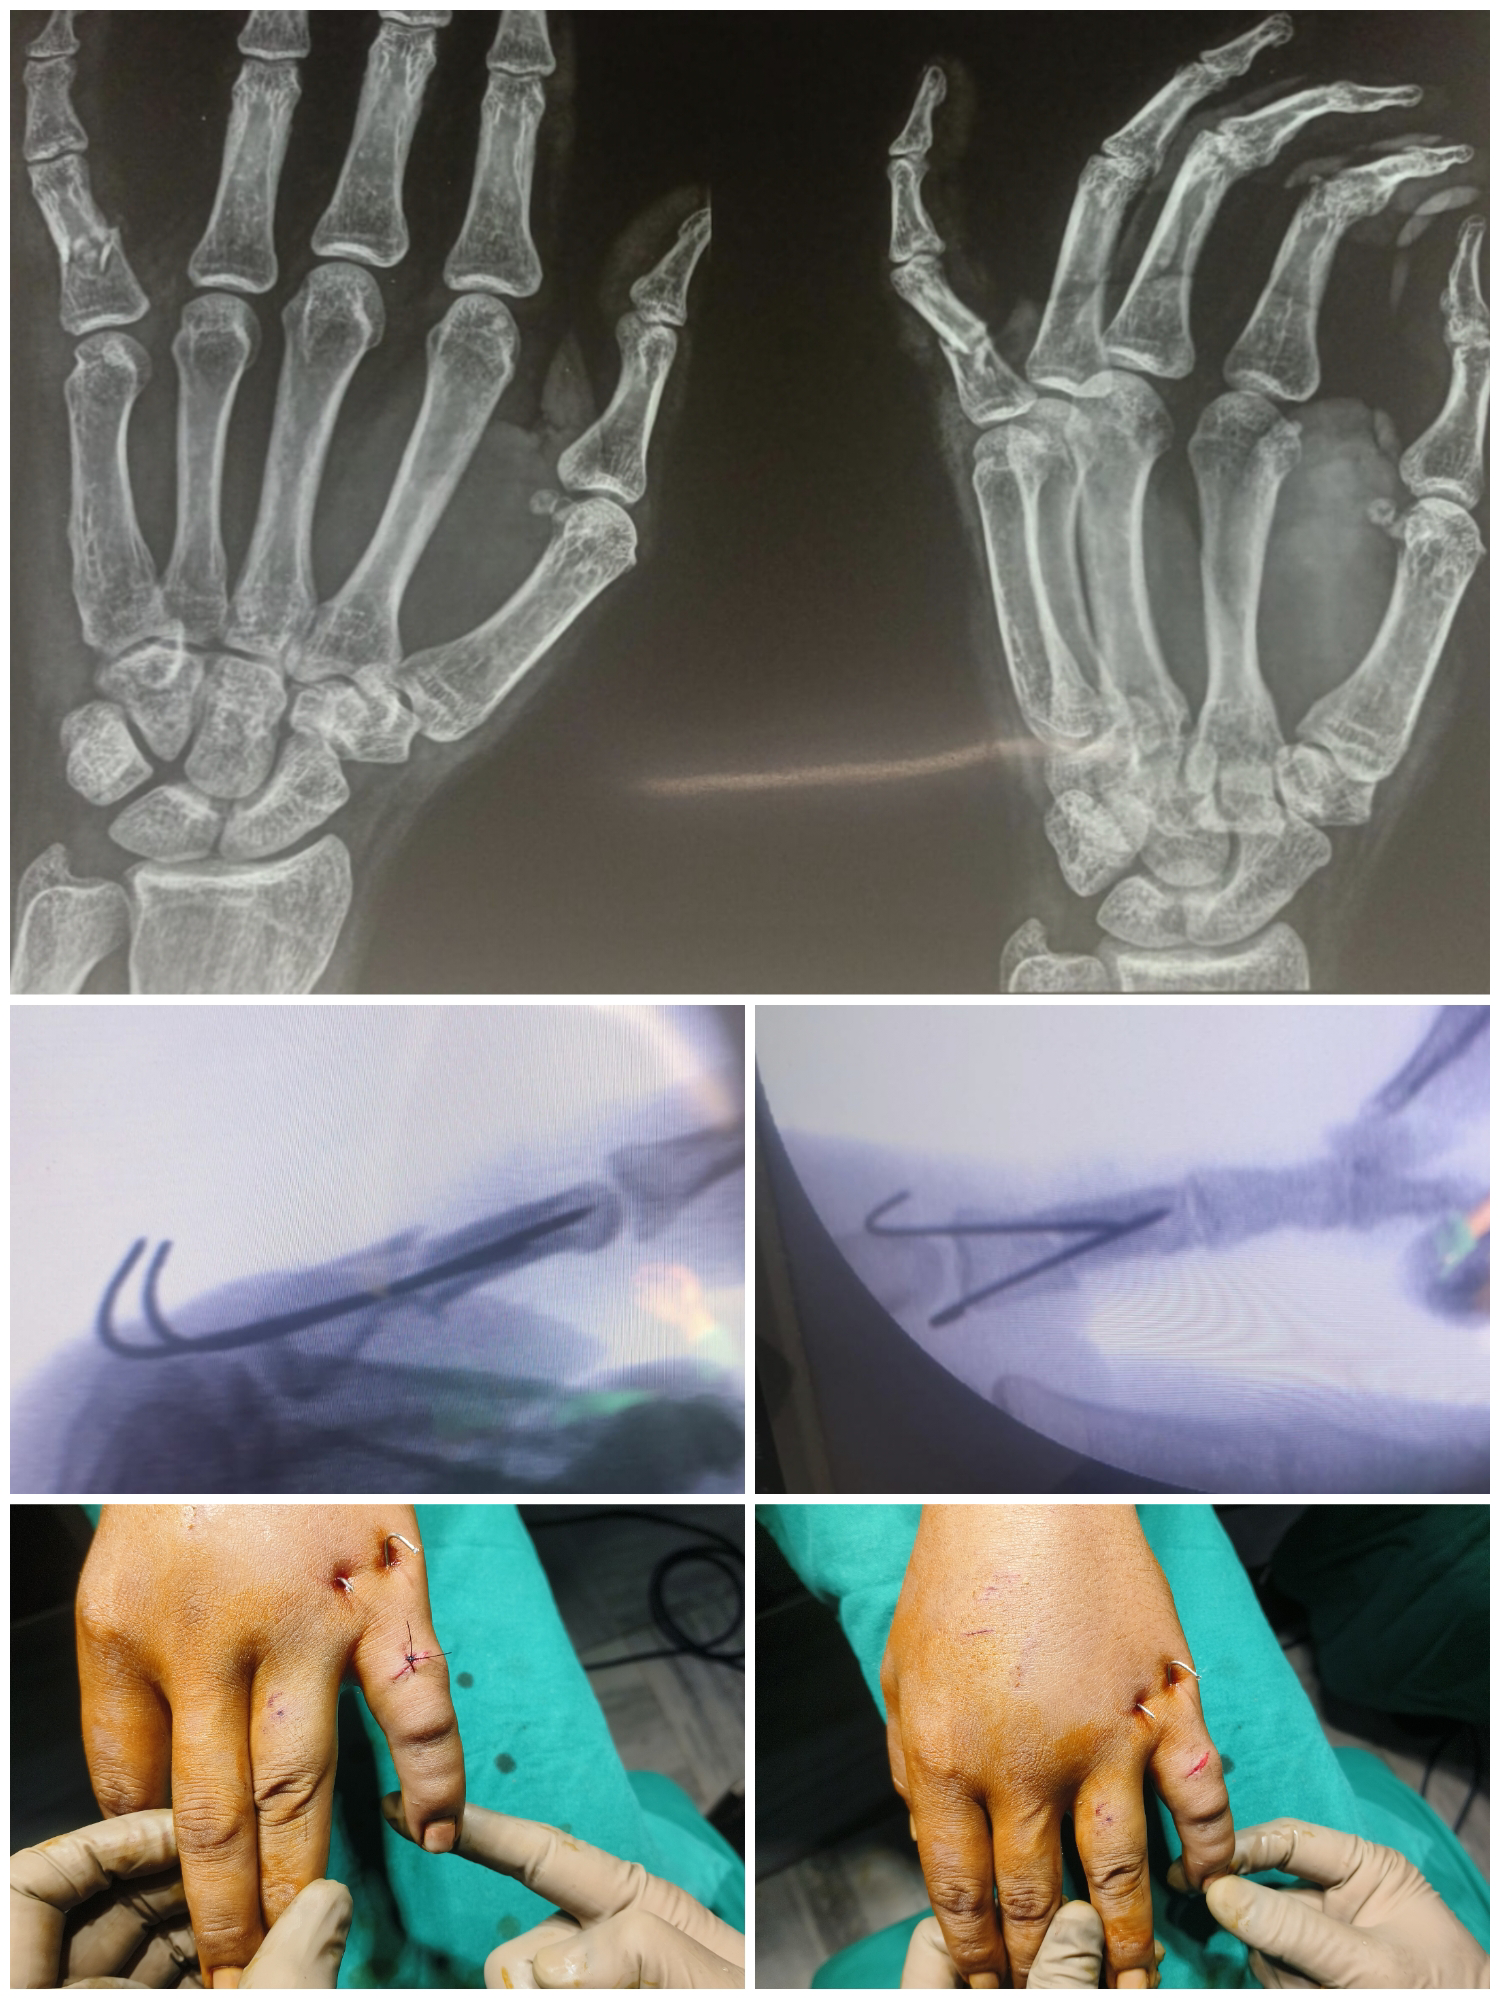

34 year old labour sustained injury to left little finger due to fall, presented with CLW over dorsum of left little finger proximal phalanx. X-ray shows comminutted fracture of left little finger proximal phalanx. Patient was operated with Closed reduction and internal fixation with two 1.5 mm k-wires.